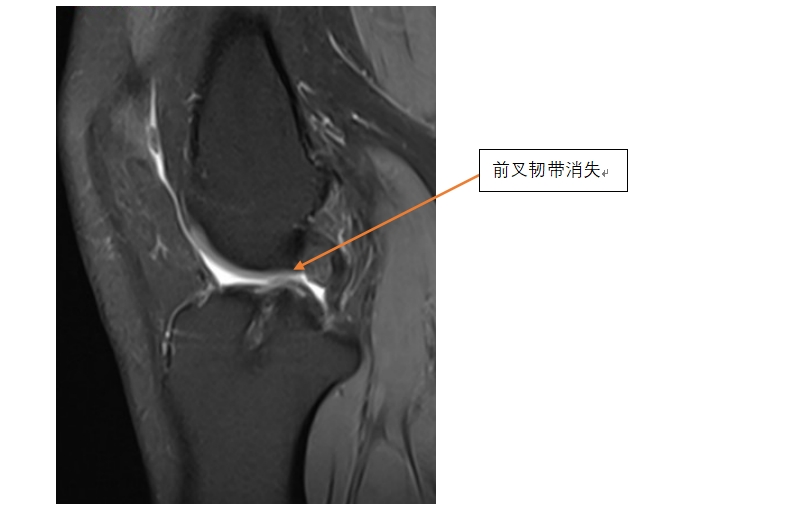

近日,我院运动医学科黄遂柱博士团队采用人工韧带(LARS韧带)成功为一位前叉韧带重建后再断裂病人实施了翻修手术。患者是一位三十多岁的女性,2年前因前交叉韧带断裂在外省一家医院进行了自体腘绳肌肌腱重建手术,3月前因受伤手术后的膝关节再次出现肿痛、活动受限,在当地医院做磁共振检查提示重建的前叉韧带已经断裂并吸收。患者得知情况后非常焦虑,害怕再次手术,尤其害怕再次取自体的肌腱。患者慕名来到我院运动医学科找到黄遂柱博士,黄博士根据该患者的情况为其推荐了人工韧带进行翻修的手术方法,可以避免再次取自体肌腱,同时术后恢复更快。